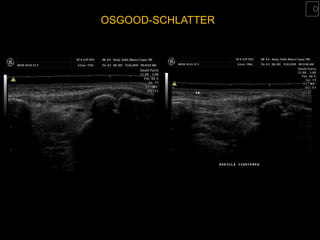

OSGOOD-SCHLATTER